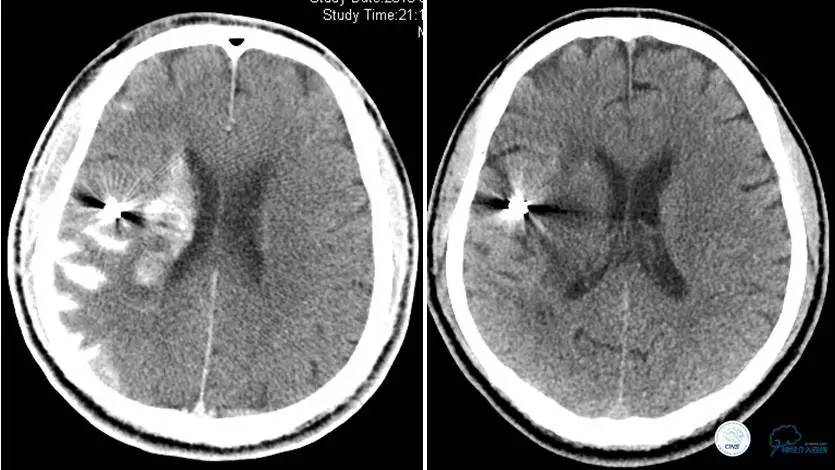

▼术后即刻CT,梗死灶内再灌注出血。

患者无症状,中性治疗。4月21日电话随访,一般情况好,当地CT示出血吸收期。

术后即刻和6天后CT,患者无明显临床症状。